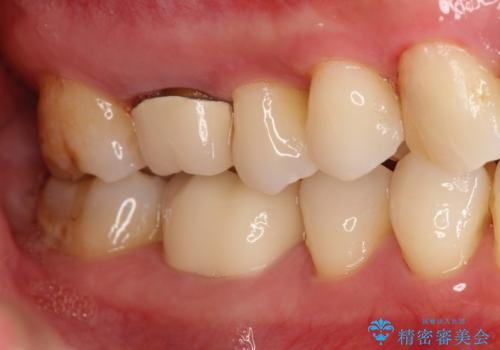

やはり内部では少量の虫歯がありましたので、拡大鏡使用して虫歯を除去しました。

虫歯の取り残した場合は将来的に再治療が高い確率で必要となります。

今回精度の高い治療を行うことで、再治療の可能性を限りになく小さくできました。